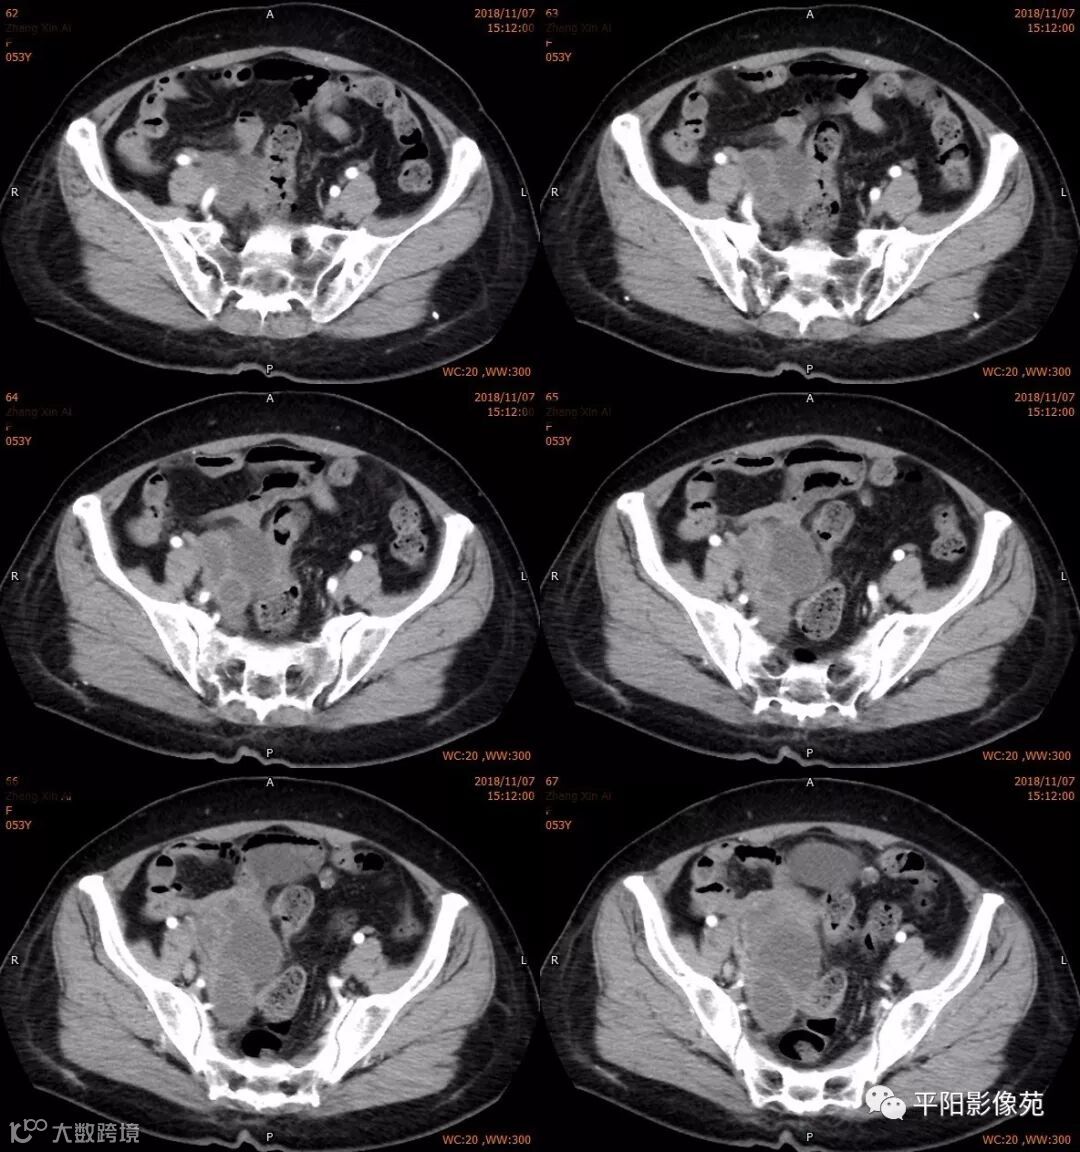

右附件区薄壁囊性病变,壁明显强化,边界不清,供血动脉源自子宫动脉,且局部动脉血管增多;其内侧可见卵圆形无强化囊性病灶。

附件区病变多见于卵巢,以囊性为主的病灶多为卵巢囊肿、粘液/浆液性囊腺瘤、皮样囊肿等,这些病灶都具有鲜明瘤体结构,且壁强化多为轻-中度,供血动脉多源自卵巢动脉;而本例患者右附件区薄壁囊性病灶,多位置观察形态为迂曲管状,且壁有明显延迟强化,供血动脉源自子宫动脉,较对侧血管丰富,故而考虑源自输卵管或子宫病变,但子宫发生的薄壁囊性病变较少,多见于子宫肌瘤囊变,完全囊变者少见,且形态轮廓与肌瘤相同为球形故而排除,结合患者腹痛前有感冒病史,且有压痛,因此考虑输卵管积脓可能。其内侧无强化囊性肿块,考虑卵巢囊肿可能。